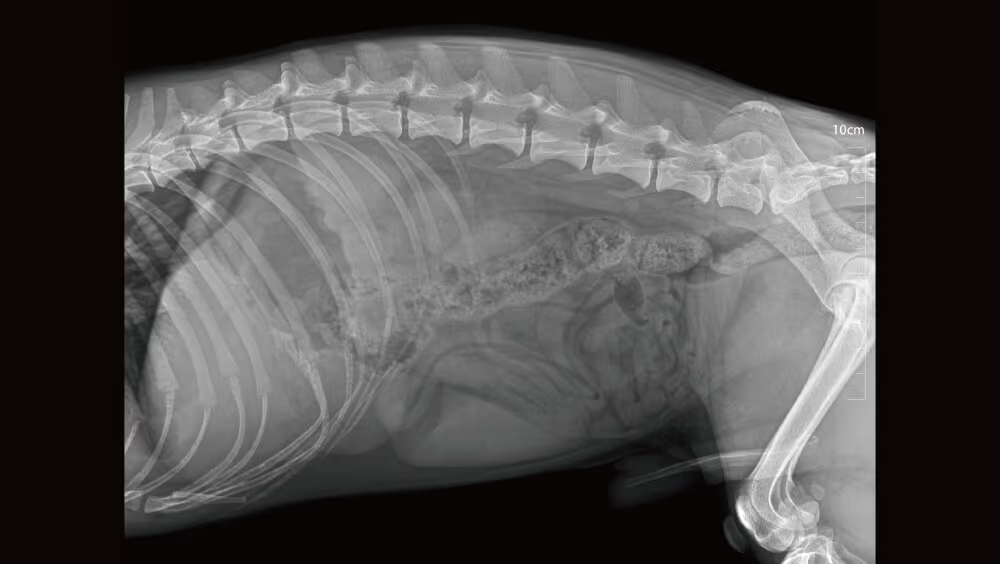

VetiX S380, modern dijital radyografi standardını belirler. Yüksek kalite, kolay kullanım ve kullanıcı dostu tasarımı ile bu sistem, veteriner hekimlere güvenilir teşhis koyma ve hasta bakımını en üst düzeye çıkarma imkanı sunar.

460kHz Radyasyon kalitesini artırın, radyasyon gürültüsünüazaltın ve görüntü kalitesini artırın.